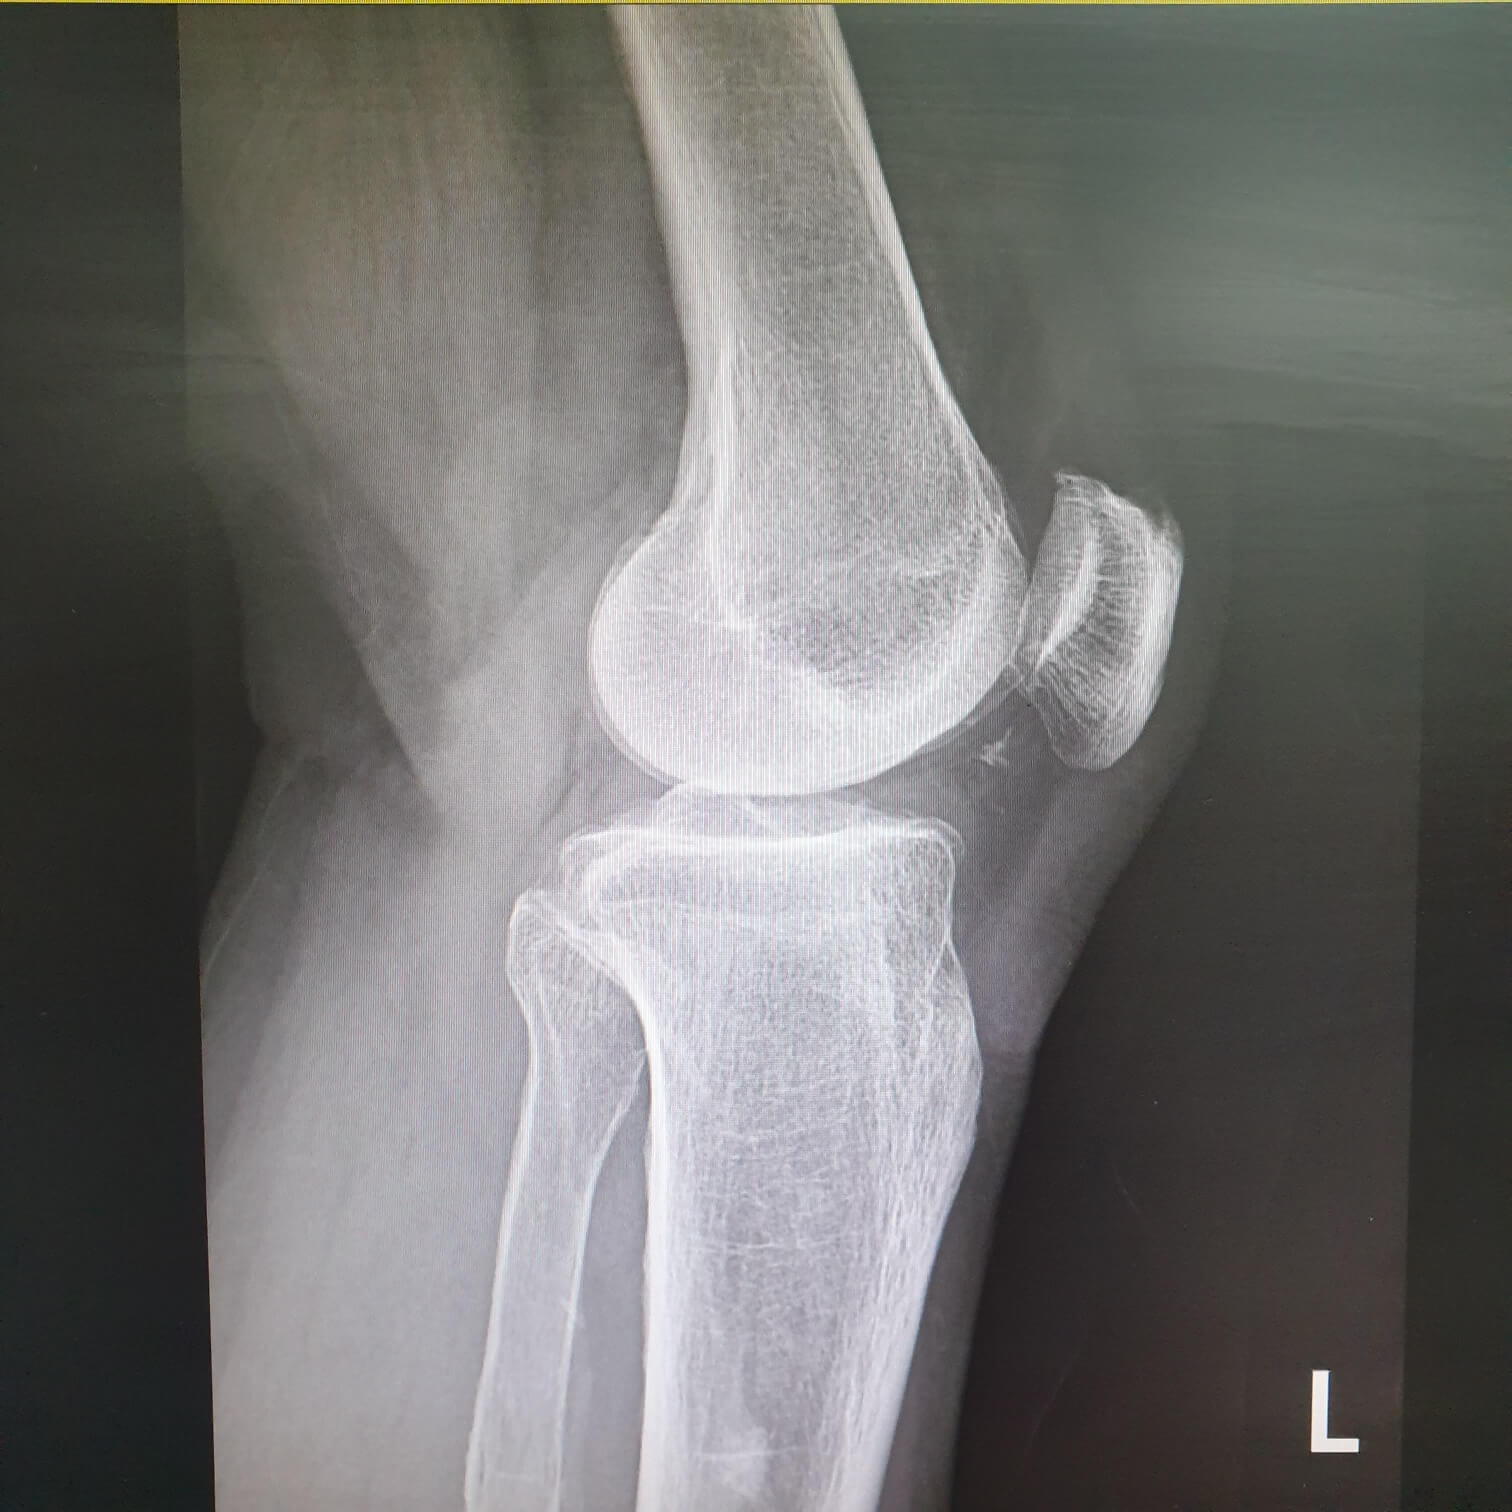

무릎의 퇴행성 관절염이나 류마티스 관절염으로 인해 관절이 파괴 된 경우 관절 연골과 뼈를 제거하고 관절 표면을 금속 삽입물과 고밀도 플라스틱으로 교체 삽입하는 수술을 말합니다.